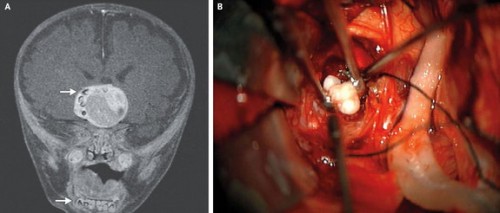

Έναν όγκο, ο οποίος, μάλιστα, διέθετε καλοσχηματισμένα δόντια, εντόπισαν και αφαίρεσαν Αμερικανοί γιατροί από τον εγκέφαλο ενός μωρού τεσσάρων μηνών, όπως δημοσιεύεται στο «Live Science».

Όπως αποκαλύφθηκε από την απεικονιστική εξέταση, υπήρχε ένας όγκος με δομές πολύ όμοιες με αυτές των δοντιών της κάτω γνάθου.

Η χειρουργική αφαίρεση από το κέντρο του εγκεφάλου έφερε πράγματι στο φως έναν όγκο με διαστάσεις 4,1Χ4Χ3,5 εκατοστών, που περιείχε αρκετά πλήρως διαμορφωμένα δόντια.

Σύμφωνα με την ανάλυση που ακολούθησε, το παιδί έπασχε από κρανιοφαρυγγίωμα, ένα πολύ σπάνιο εγκεφαλικό όγκο, ο οποίος μπορεί να γίνει μεγαλύτερος από μπάλα του γκολφ, όμως δεν εξαπλώνεται μεταστατικά στο υπόλοιπο σώμα.

«Δεν βλέπεις κάθε μέρα δόντια σε οποιοδήποτε όγκο του εγκεφάλου. Τα κρανιοφαρυγγιώματα συνήθως περιέχουν εναποθέσεις ασβεστίου, όμως, όταν βγάλαμε ένα κανονικό δόντι, αυτό σίγουρα ήταν κάτι διαφορετικό», δήλωσε ο νευροχειρουργός Νάρλιν Μπίτι του Ιατρικού Κέντρου του Πανεπιστημίου του Μέριλαντ.